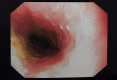

Figure 6

Figure 6. Endoscopy showing trichobezoar in the stomach